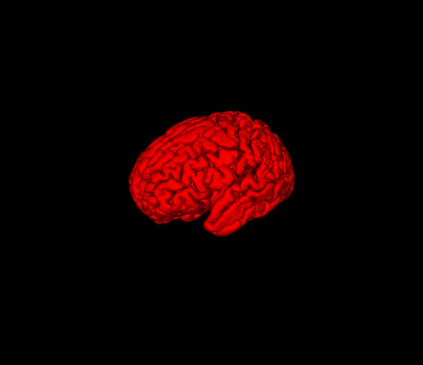

Fetal cortical plate segmentation is essential in quantitative analysis of fetal brain maturation and cortical folding. Manual segmentation of the cortical plate, or manual refinement of automatic segmentations is tedious and time-consuming. Automatic segmentation of the cortical plate, on the other hand, is challenged by the relatively low resolution of the reconstructed fetal brain MRI scans compared to the thin structure of the cortical plate, partial voluming, and the wide range of variations in the morphology of the cortical plate as the brain matures during gestation. To reduce the burden of manual refinement of segmentations, we have developed a new and powerful deep learning segmentation method. Our method exploits new deep attentive modules with mixed kernel convolutions within a fully convolutional neural network architecture that utilizes deep supervision and residual connections. We evaluated our method quantitatively based on several performance measures and expert evaluations. Results show that our method outperforms several state-of-the-art deep models for segmentation, as well as a state-of-the-art multi-atlas segmentation technique. We achieved average Dice similarity coefficient of 0.87, average Hausdorff distance of 0.96 mm, and average symmetric surface difference of 0.28 mm on reconstructed fetal brain MRI scans of fetuses scanned in the gestational age range of 16 to 39 weeks. With a computation time of less than 1 minute per fetal brain, our method can facilitate and accelerate large-scale studies on normal and altered fetal brain cortical maturation and folding.